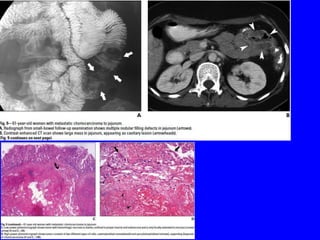

• The radiologic appearance mainly depends on the histologic

characteristics of the lesion, including the degree of vascularity

relative to the growth rate&the desmoplastic capability.

Diagnosis:

• Can be difficult due to an often prolonged tumor-free interval &

benign appearance of the lesions &gastric metastasis may

occasionally mimic a gastric primary.

• Stomach is the most frequent GIT site for metastatic breast cancer.

• The most characteristic endoscopic finding of metastatic lobular

breast carcinoma is a linitis-plastica-like appearance,showing tumor

infiltration along the stomach wall with mural thickening of the

involved segment & submucosal infiltration,makes the diagnosis

difficult on endoscopic & imaging exams.

• Advances in imaging techniques like CT scan &EUS with guided

biopsy have aided confirmation of the diagnosis.